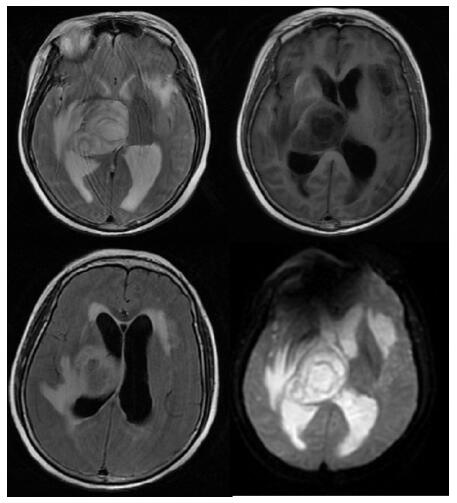

| A:右侧丘脑、左侧岛叶病变,伴脑室扩张;B:双侧脑室钻孔引流术后改变,脑室扩张较前(2019-09-29)好转,右侧丘脑、左侧岛叶病变伴出血 图 2 患者2019-09-29头颅CT平扫(A)和2019-09-30头颅CT平扫(B) |

转入ICU后呼吸机辅助通气、甘露醇100 mL/8 h静滴脱水、头孢呋辛1.5 g/12 h静滴抗感染,肠内营养等支持治疗。当晚血常规:白细胞13.3×109/L,中性粒细胞百分比85.3%,C反应蛋白17.1 mg/L,降钙素原0.64 ng/mL。脑室外引流术后次日血化验:白细胞16.6×109/L,中性粒细胞百分比92.8%,C反应蛋白78.4 mg/L;从脑室外引流管留取脑脊液检验:有核细胞6×106/L,红细胞1 960×106/L,蛋白含量1.717 g/L,葡萄糖4.72 mmol/L,细菌培养阴性,涂片未找到细菌;复查头颅CT示:脑室扩张好转,右侧丘脑、左侧岛叶病变伴出血(图 2);胸部CT示,两肺间质性肺炎下叶为著,较前(2019年6月21日)部分好转(图 3)。考虑到炎症指标升高,遂改哌拉西林他唑巴坦3.375 g/12 h静滴抗感染。此后经脑室外引流管反复留取脑脊液送检涂片及培养均阴性。术后第5天行“导航下立体定向颅内病灶活检术+双侧omaya囊置入术”,术中穿刺液呈黄色黏稠脓性,考虑脑脓肿,留取脓液送高通量测序(next-generation sequencing, NGS),并升级为美罗培南2 g/8 h联合利奈唑胺0.6 g/12 h静滴抗感染治疗。术后第7天患者突发血压升高、瞳孔不等大,昏迷程度加深;急查头颅CT示,双侧脑室钻孔引流术后改变,双侧侧脑室引流管走形区出血伴血肿形成;右侧丘脑区积液、积血,双侧脑室积血新发(图 4),甘露醇加量至250 mL/8 h联合地塞米松5 mg/6 h静滴加强脱水;当日术中脓液高通量测序结果回报:皮疽诺卡菌(序列数52 867个)、支气管戈登菌(序列数10个)。确诊脑诺卡菌病,抗菌治疗方案改为亚胺培南西司他丁0.5 g/6 h静滴,联合利奈唑胺0.6 g/12 h和复方磺胺甲恶唑片(0.48 g/片)3片/6 h口服。此后患者仍伴低热,炎症指标呈上升趋势。术后2周患者再次突发血压升高、瞳孔不等大、对光反射消失、神志深昏迷,急查头颅CT示再发脑疝(图 5),急诊行“去骨瓣减压术+脑内血肿清除术”,术后患者仍呈深昏迷状态,双侧瞳孔散大、对光反射消失,次日自动出院。